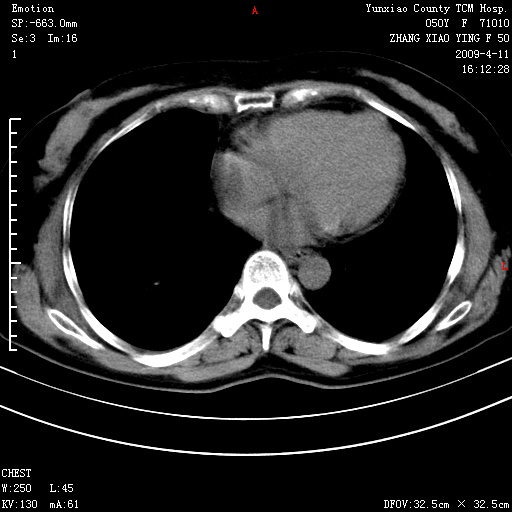

标题: CT19324:胸闷1周伴咳嗽 [打印本页]

标题: CT19324:胸闷1周伴咳嗽

病灶周围肺纹受压移位走行较柔和,余肺里实质均匀,纹理如常,肺间质无显著纤维化,支持考虑孤立性肺囊肿

考虑右肺中叶肺囊肿。